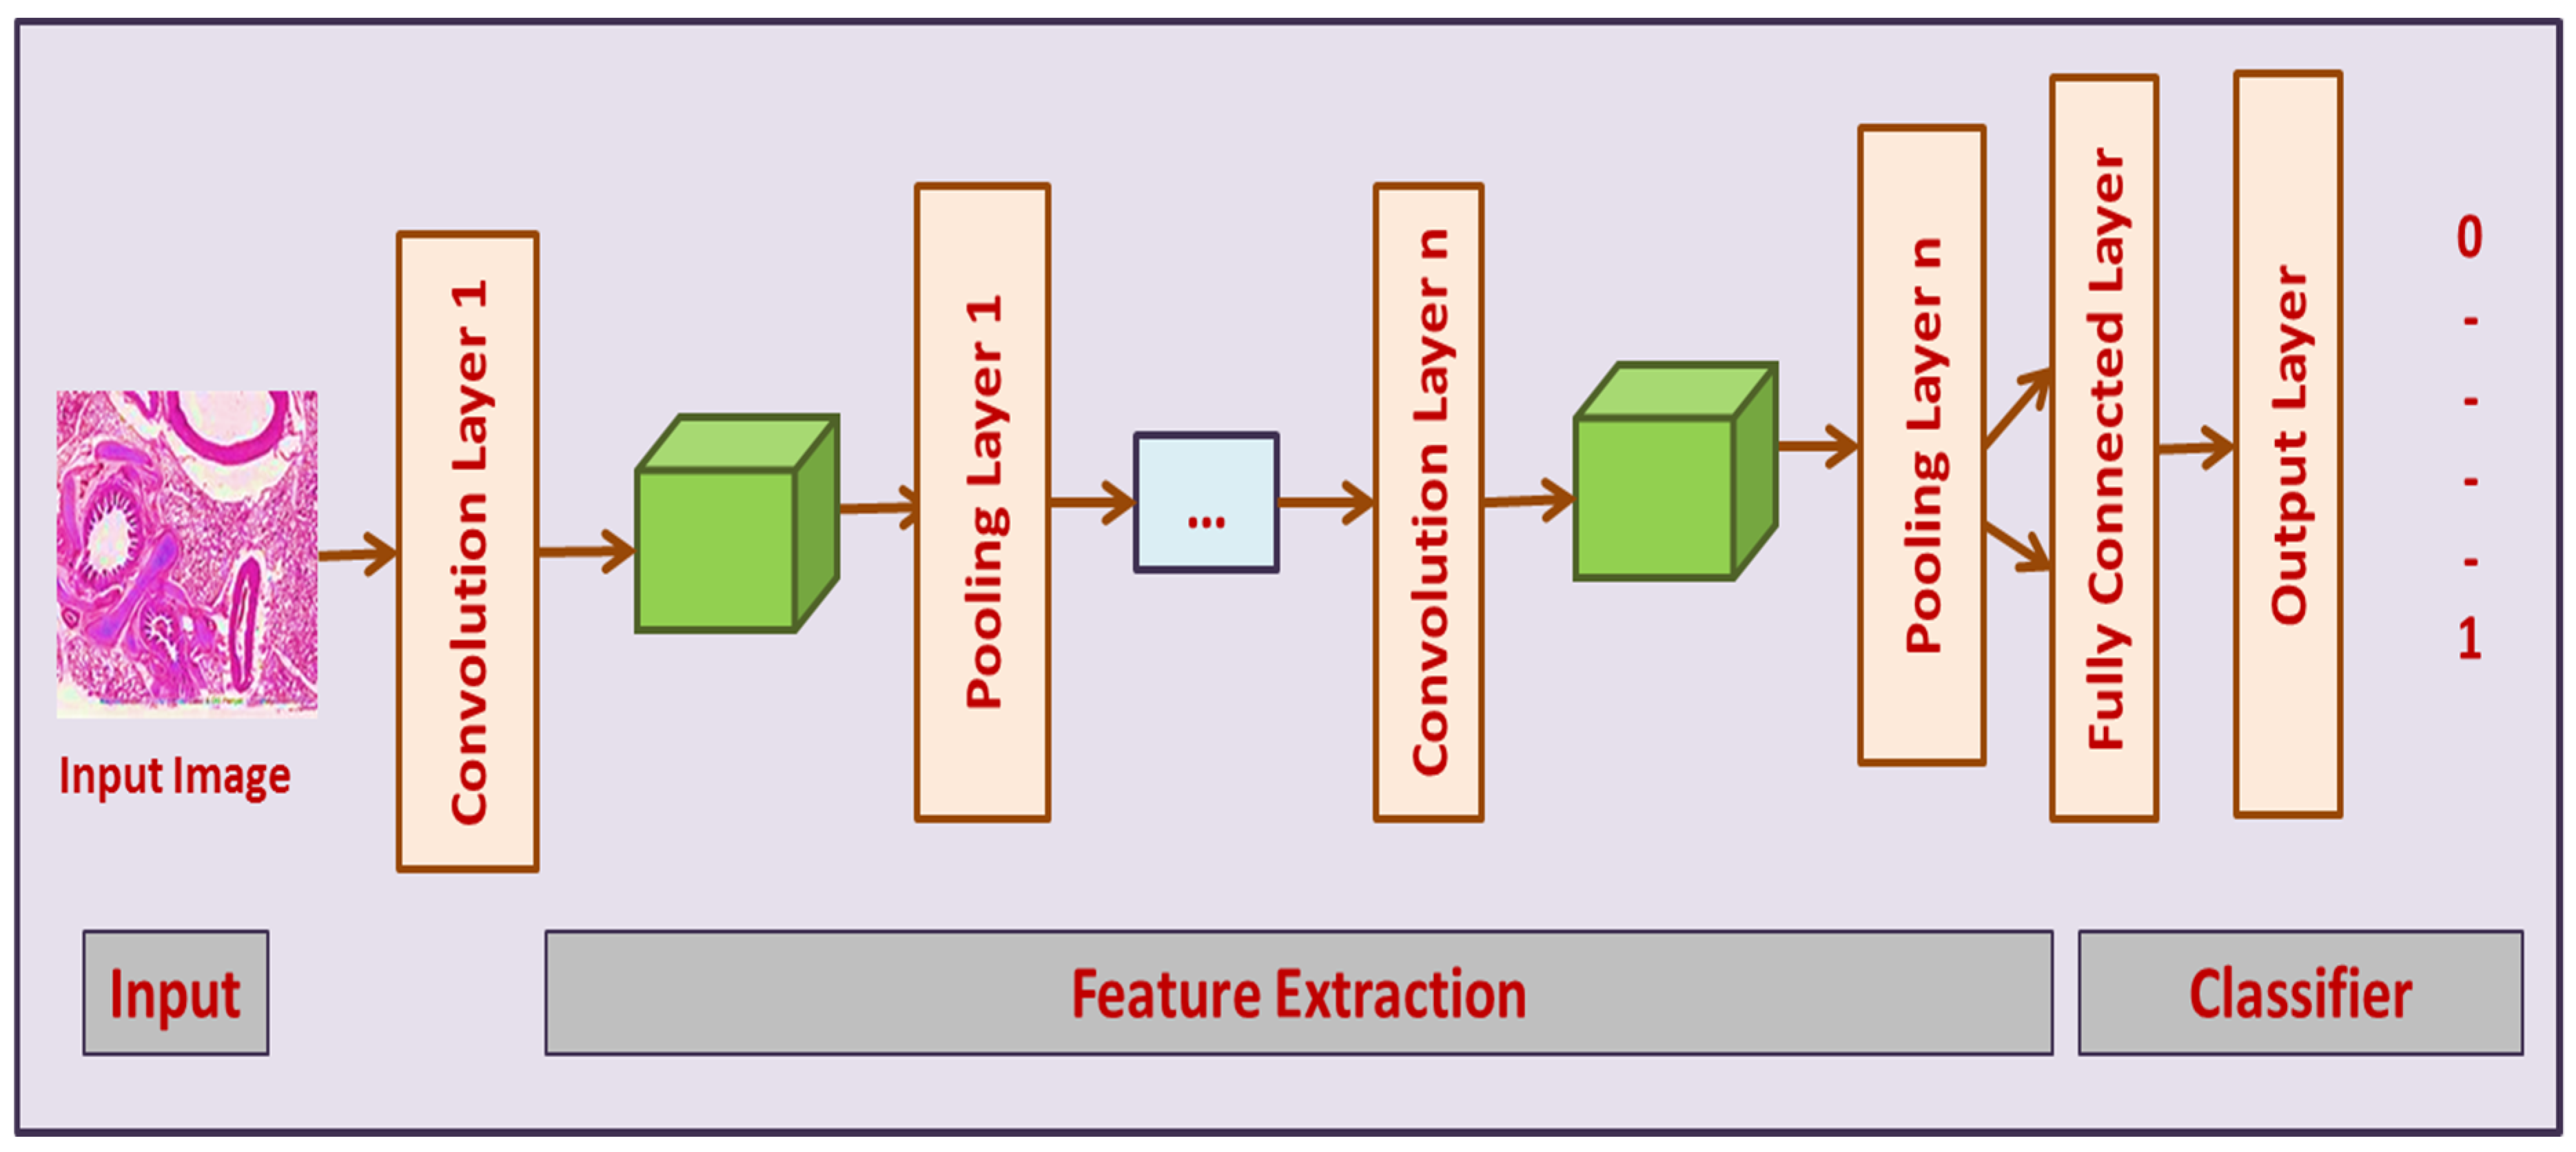

3.3.1. Convolutional Neural Networks (CNN)

3.3.3. CNN-GRU